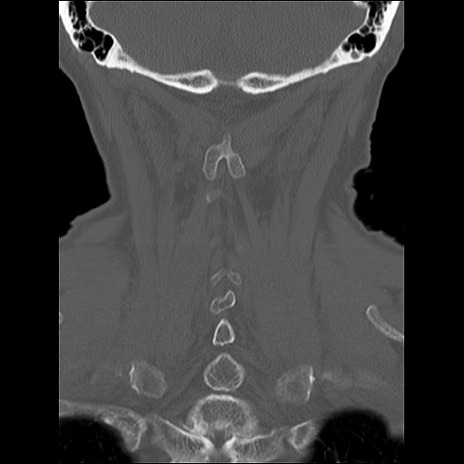

症例48 頚椎CT(冠状断像)

頚椎CT